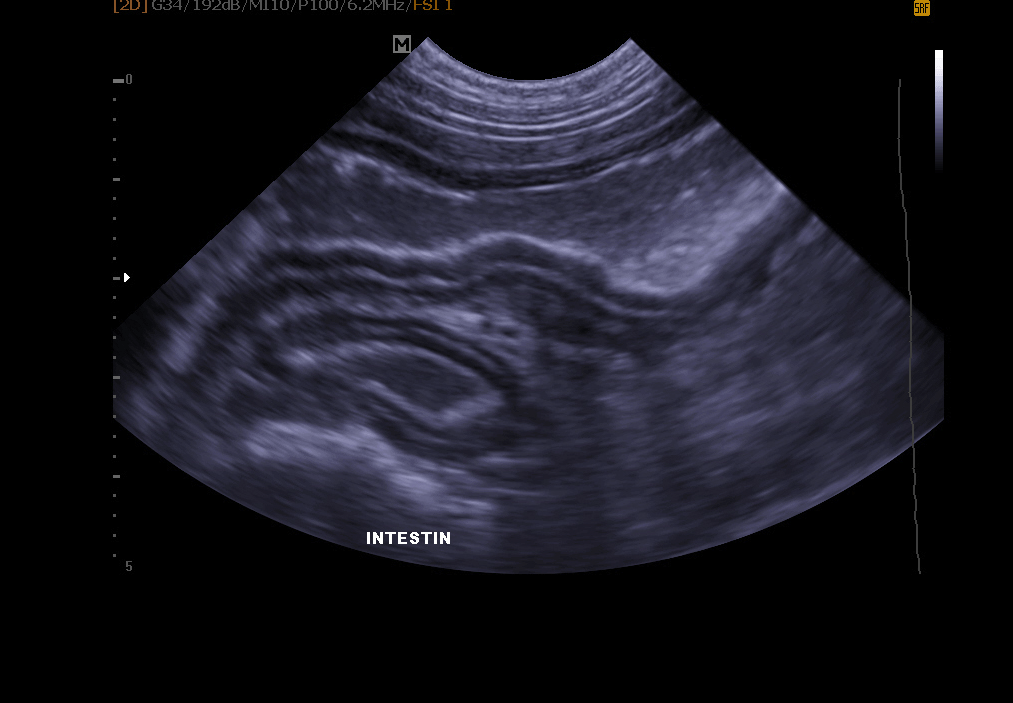

Abdominal ultrasound: it allows exploration of the bladder (search for stones, polyps, tumor), kidneys, spleen, liver, pancreas and other abdominal organs.